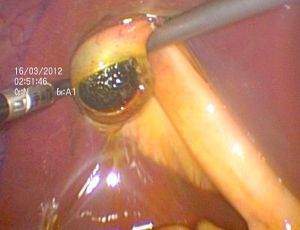

(六)腹腔鏡聯合膽道鏡微創保膽取石術

這種保膽取石方法結合了腹腔鏡和膽道鏡的優點。其同時避免了小切口,做到了儘可能的微創,又使用膽道鏡保證結石的取盡。但由於術中需膽道鏡探查及腹腔鏡下縫合結紮,故操作難度相對較大,準入門檻高。

完全腹腔鏡保膽取石又稱腹腔鏡聯合膽道鏡保膽取石術,其具有腹腔鏡輔助的小切口保膽取石術的優點,同時避免了小切口,做到了儘可能的微創,但由於術中需膽道鏡探查及腹腔鏡下縫合結紮,故操作難度相對較大,準入門檻高,目前僅在腹腔鏡技術較為成熟的醫院開展。